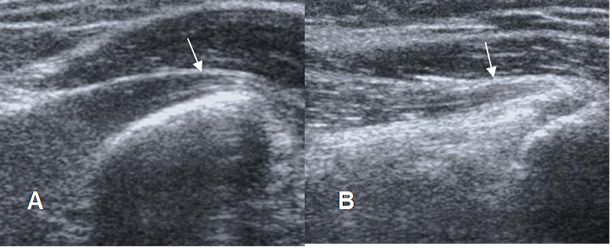

Los ligamentos son engrosamientos fibrosos de la cápsula y se valoración requiere de imágenes coronales oblicuas y axiales de RM. (1). (Fig 17, 18, 19, 20 y 21). La prueba de elección para su valoración, es la ArtroRM guiada con fluoroscopia. (9).

Fig 19. Ligamento anular normal.

RM axial en T1. Inserción anterior (Flecha delgada) y posterior (Flecha gruesa).